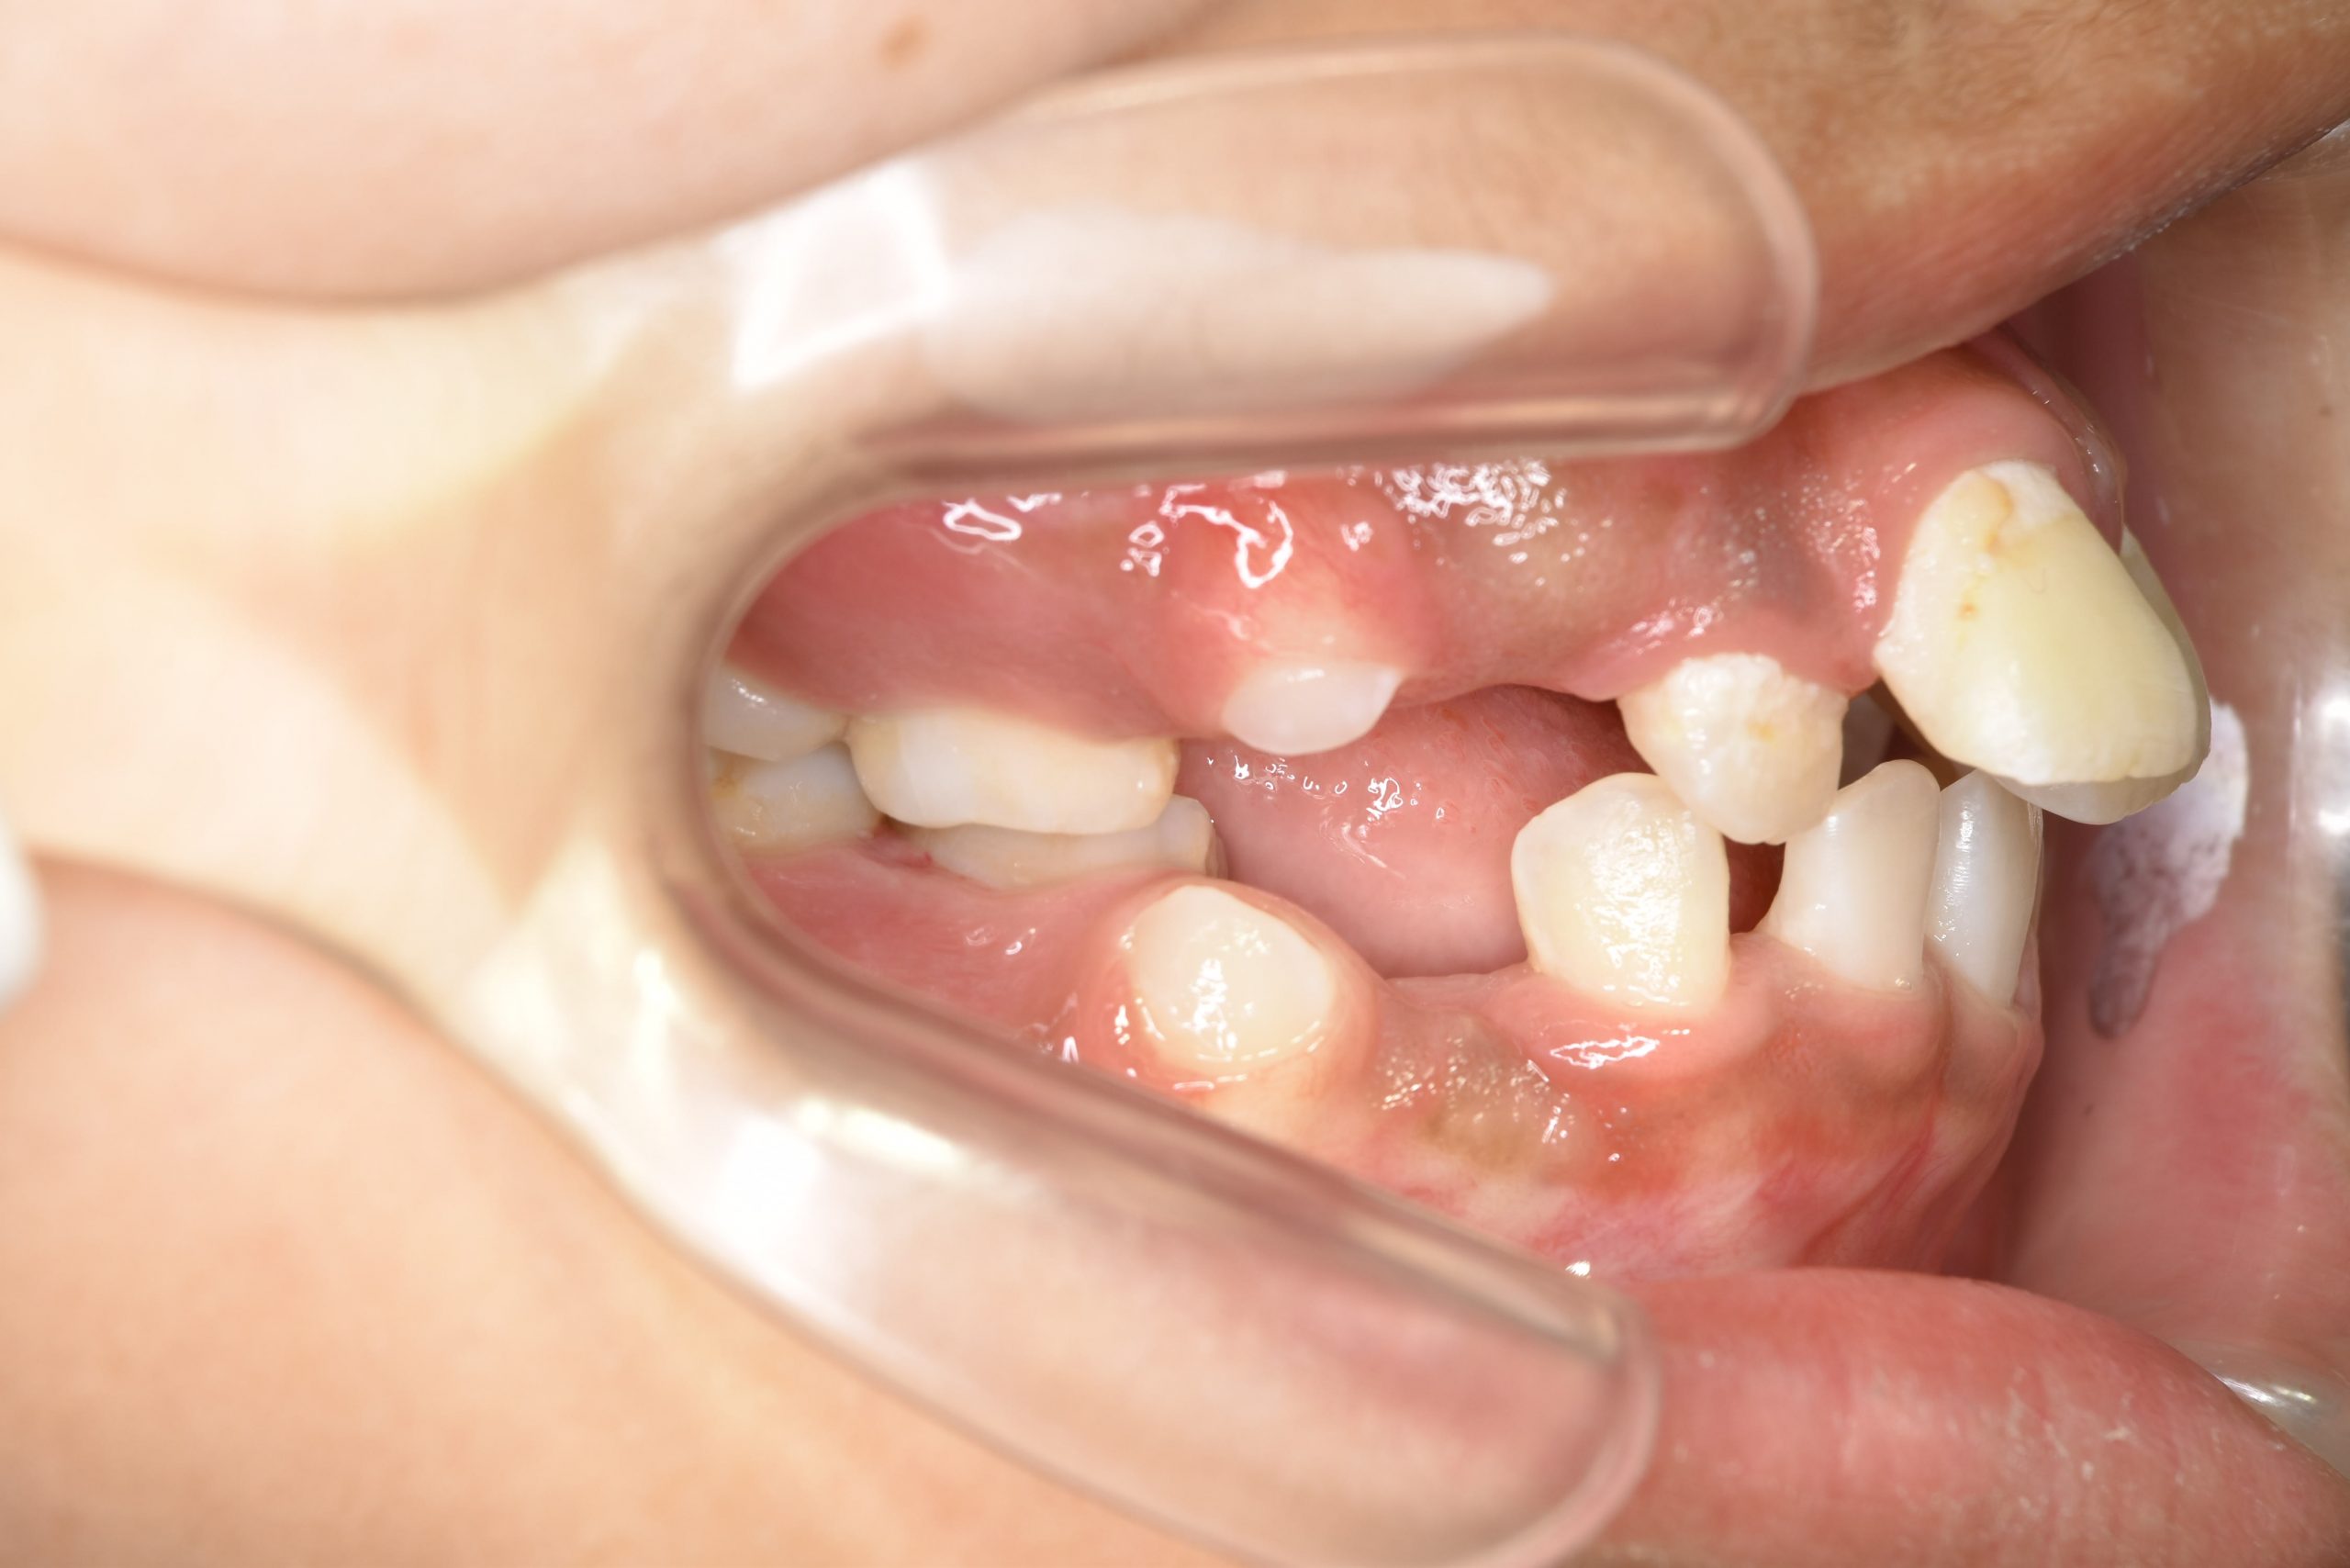

ビフォー

全顎ワイヤー矯正 症例_474

主訴 歯並びがガタガタで前歯が出ている

施術内容 小児矯正1期治療

治癒期間 1年5か月間

費用 1,020,800円(税込)